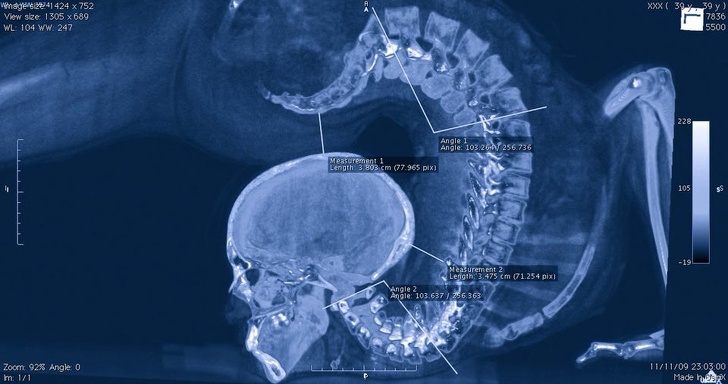

4. Комп'ютерна томографія гімнастки, що виконує вправу